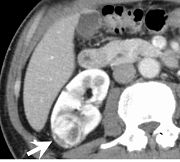

術前CT精査の例(腎細胞癌)

術前精査では、組織診断を推定するための造影 dynamic study(図1-4)と体幹部を含めたスキャンによる病期診断、また、手術シュミレーションに活用できる立体像(図5,6)作成を行っています。

| 図3 造影 dynamic CT 実質相 病変は再び低吸収となる |

図4 造影 dynamic CT 排泄相 病変はさらに低吸収が明瞭となる |